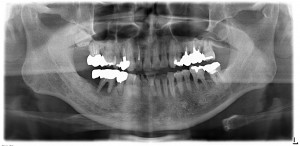

治療前のレントゲンですが、右下の6番部位は大きな骨吸収がみられます。